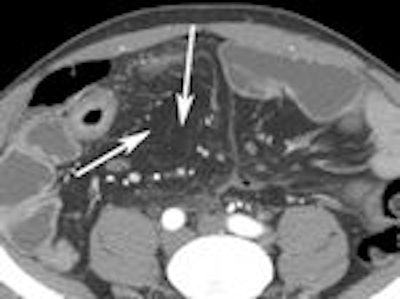

The following images from Higgins' study illustrate some of the clinically relevant findings about Crohn's disease that can be made with CTE.

Left: Bowel wall thickening. Right: Extraluminal fluid.